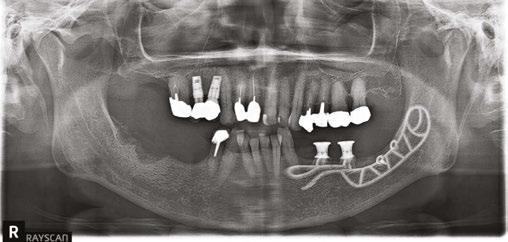

Our patient is consulting for pain in the right mandibular molar region and difficulty chewing (Figure 3).

Figures 2A and 2B: Panthera Dental platform interface; vestibular (2A) and lingual (2B) views of the subperiosteal implant Figure 3: Initial panoramic image Figures 4A-4C: Visualization of the subperiosteal implant in relation to the mock-up

not to undergo long and complex implant treatment. Her request is first and foremost functional. Esthetics and price are secondary concerns. We therefore offer the following treatment plan: keep the malpositioned anterior mandibular teeth with only mild gingivitis, rehabilitate the left posterior mandibular region with a subperiosteal implant, extract molars 47 and 48, and reassess the best implant solution for this region after healing.

Given the initial anatomical situation (strong resorption, significant mobile soft tissue, blockage by the tongue, V-shaped mandible), a conventional impression with a CIT and a physical mock-up with radiopaque markers are preferred.

The patient returns four months later for a clinical follow-up (Figures 12A and 12B) and X-rays (Figure 13).

The permanent dentures are then placed over a titanium frame processed by Panthera Dental and stratified in composite at the denture laboratory (Figures 14A-14C).